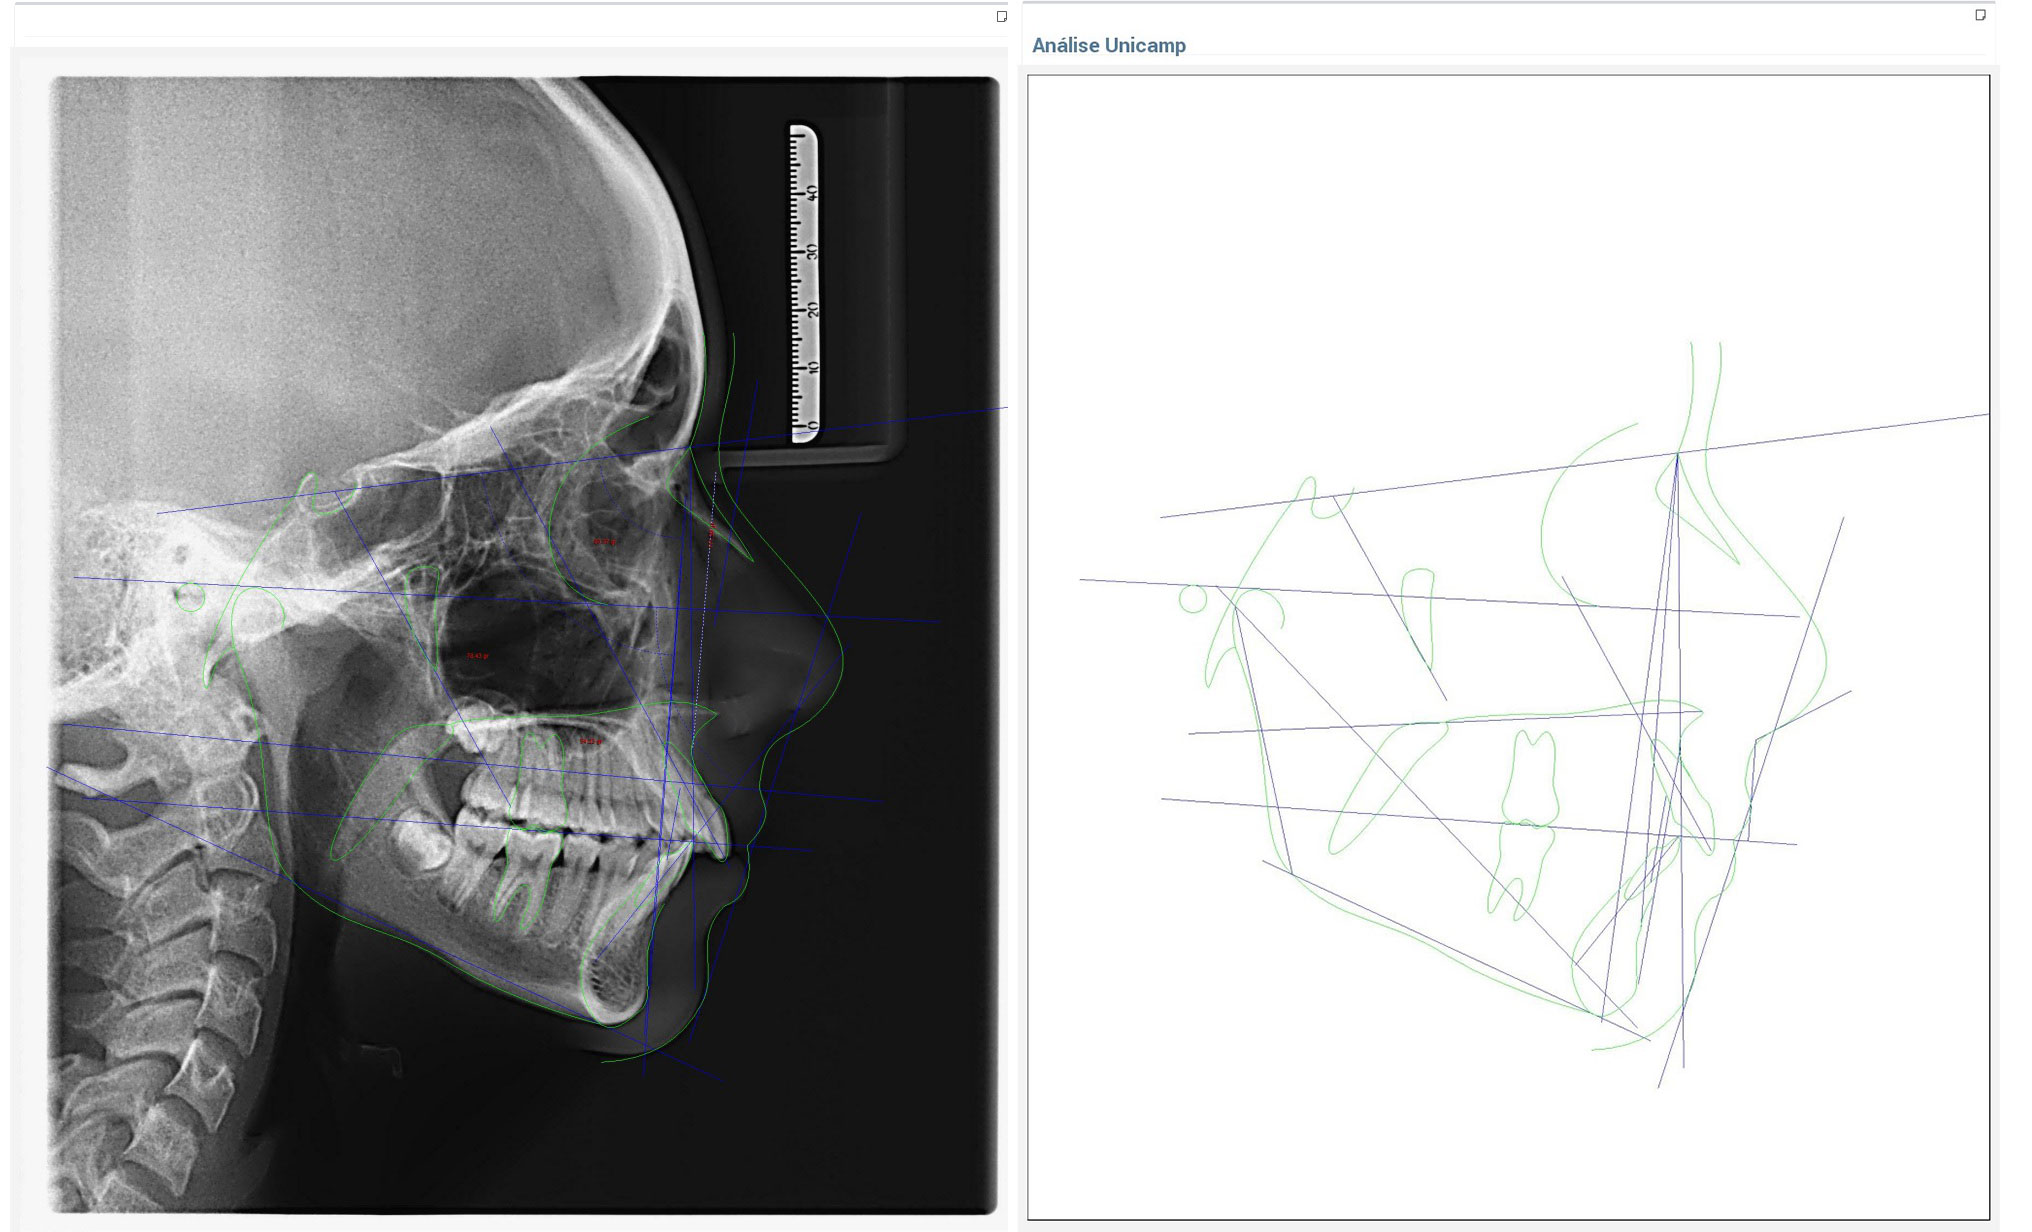

Rx Lateral - Cefálica - Telerradiografía

Análisis

Análisis Cefálicos - Cefalométricos

USP

Ricketts

Jarabak

Mc Namara

Otros..

Análisis Ortodóntico